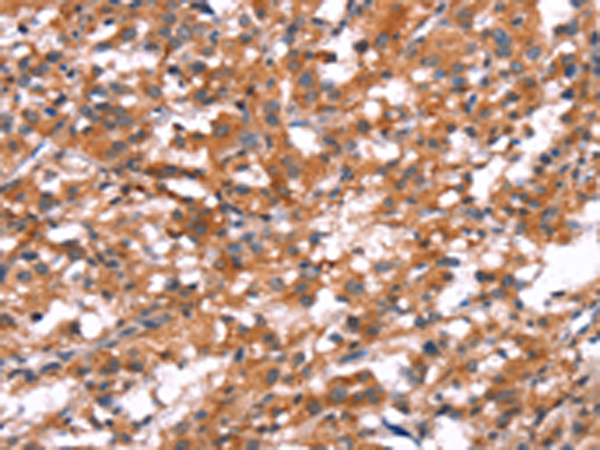

分类: 科研抗体货号: P04879别名: ATOD2应用: IHC反应种属: Human